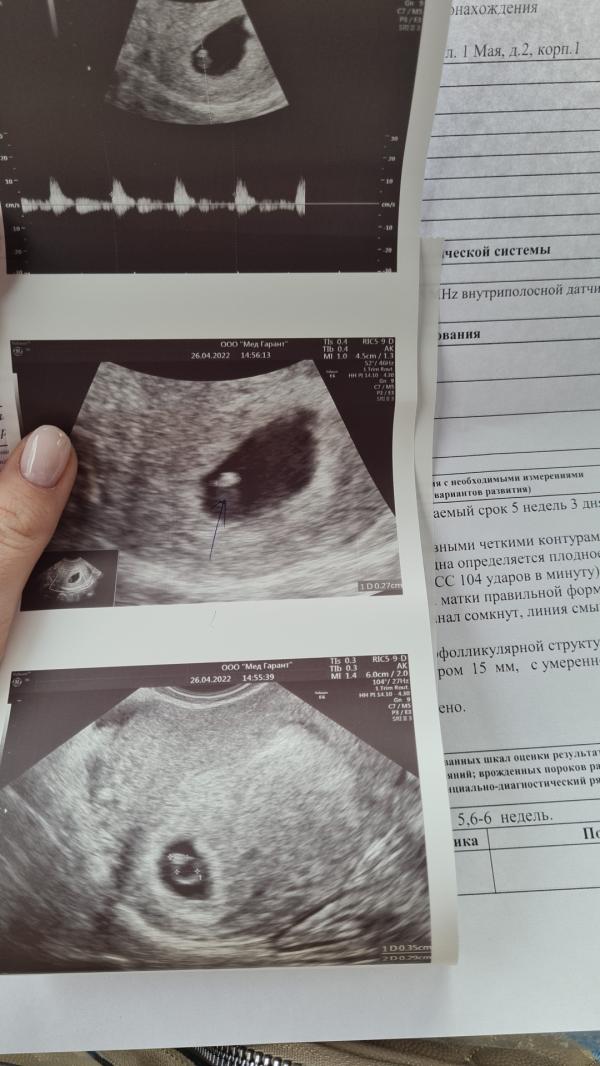

Срок 6 недель .Сердечко стучит ❤И никаких больше сомнений и мук выбора 🤗Наш маленький завиточек

На втором фото, планета во вселенной 🤗

На третьем фото , кольцо с бриллиантом☺️☺️☺️